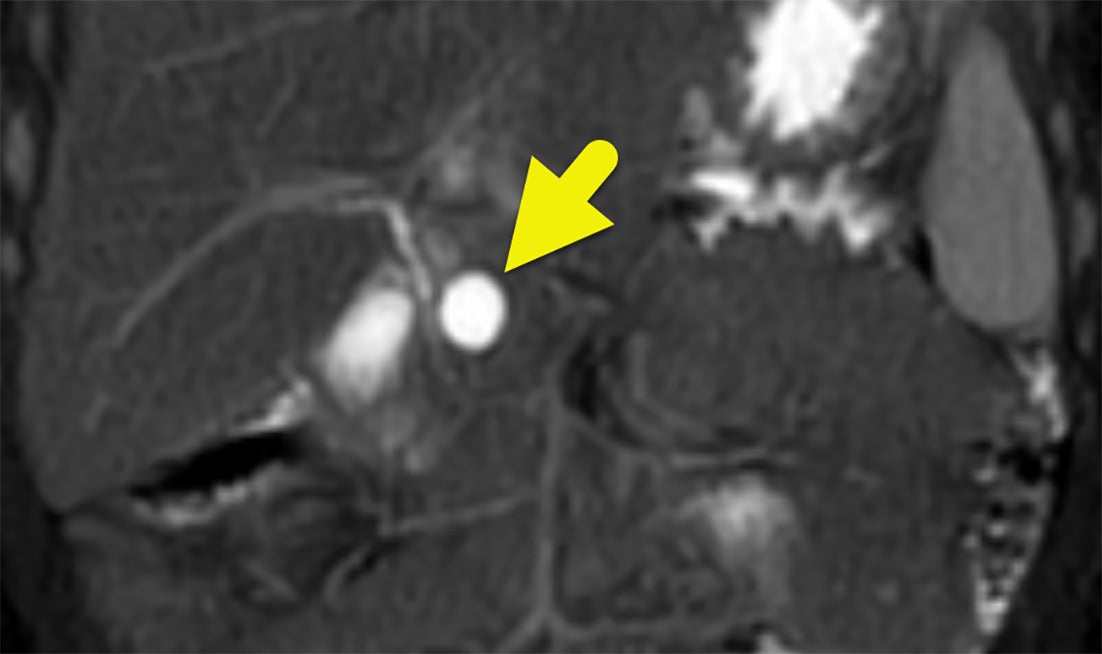

Pulmonary Artery Pseudoaneurysm